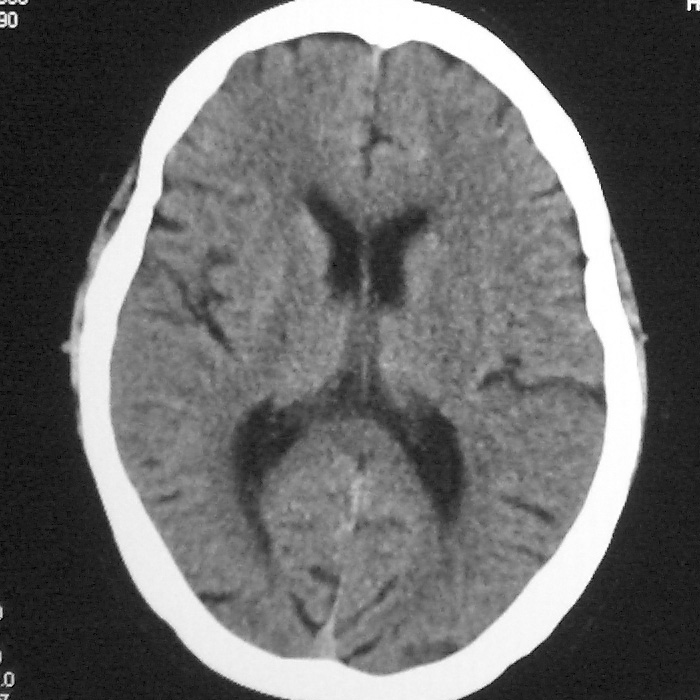

f,70y,口角歪斜、流涎、吐词不清三天

左侧大脑基底节区点状低密度影,边缘清楚,左侧腔梗或软化灶,没什么问题啊?

症状这么明显的话一般不会是单纯面神经麻痹引起的,最好做个mri,如果确实没有问题的话才能考虑面神经麻痹,毕竟这两种病的治疗和预后不一样,这个病人还有脑白质疏松。

左侧半卵圆中心腔梗应当比较明确,右侧基底节好象不明显,不好说,做个mri明确吧

双侧多发腔梗

右侧基底,左侧半卵圆中心腔梗

1、右侧基底,左侧半卵圆中心腔梗。2脑萎缩。

左侧腔隙性梗塞灶,脑萎缩。

左侧基底节区示点状低密度灶,边界清楚,密度均匀,余所示无著变。

意见:腔隙性脑梗塞(左基底节区)

各位老师,报告这么写可以吗?右侧我没有看出来。

左侧半卵圆中心,右侧基底节腔梗。再加个脑萎缩吧

双侧多发腔梗 脑萎缩